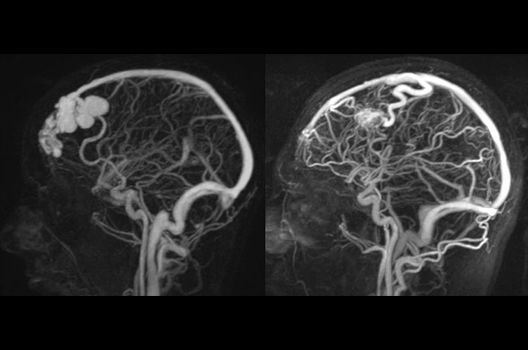

Die Magnetresonanztomographie (MRT) ist ein Verfahren, bei dem durch magnetische Kräfte Bilder des Körperinneren angefertigt werden. In der Neuroradiologie können manchmal kleinste Veränderungen schwere Folgen haben; daher forschen wir an der Entwicklung hochauflösender MRT-Sequenzen, mit denen diese Prozesse und auch einzelne Nervenfaserbahnen sichtbar gemacht werden können. Darüber hinaus sind bei vielen Erkrankungen des Gehirns die Blutgefäße betroffen. Daher arbeiten wir an der Neu- und Weiterentwicklung von MRT-Sequenzen zur Darstellung der Blutgefäße und zur Blutflussanalyse (sog. „Angio-MRT“). Einen besonderen Forschungsschwerpunkt unserer Klinik stellen die MR-Protonenspektroskopie und die funktionelle MRT dar, mit denen die Analyse einzelner chemischer Substanzen im Hirngewebe oder die Darstellung ausgewählter Hirnfunktionen möglich ist.

- Behandlung intrakranieller Gefäßmissbildungen

- Diagnostik und Therapie vaskulärer Anomalien (ZVA)

In der Neuroradiologie sind wir häufig mit Fragestellungen konfrontiert, die mehrere Fachgebiete oder auch Methoden betreffen. So arbeiten wir auch in der Forschung intensiv mit anderen Abteilungen des Universitätsklinikums zusammen, um Prozesse und Techniken bei der Diagnostik und Therapie neurovaskulärer Erkrankungen und vaskulärer Anomalien zu optimieren.